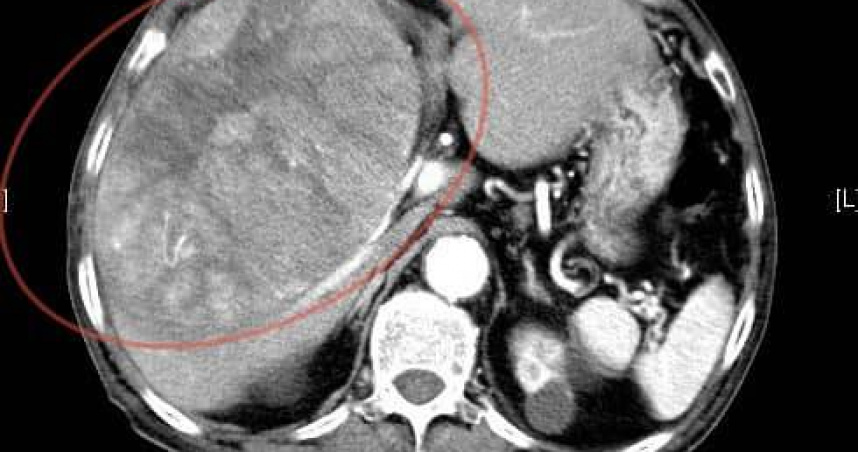

老翁肝臟有個15公分大的腫瘤,剛開始治療不久便病逝。(圖/翻攝自臉書/錢政弘 胃腸肝膽科醫師)

錢政弘透露,約2個多月前,阿公開始出現上腹疼痛和胃酸逆流,於是到他的門診求助,由於患者疼痛的部位偏右上腹部,且右側肋骨下方有壓痛,初步懷疑是膽囊問題,於是安排腹部超音波檢查,結果發現肝臟有個15公分大的腫瘤,後續CT檢查證實已經是晚期肝癌,無法手術,治療沒多久就離世了。